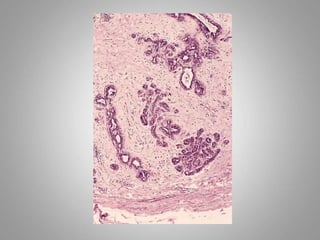

Teratoma:

– Teratoma contains recognizable mature or

immature cells or tissues representative of more

than one germ-cell layer and some times all

three.

– Teratomas originate from totipotential cells such

as those normally present in the ovary and testis.

• Such cells have the capacity to differentiate into any

of the cell types found in the adult body.

• So they may give rise to neoplasms that mimic

bone, epithelium, muscle, fat, nerve and other

tissues.

• Most common sites are: ovary, testis

Teratoma: – Teratoma containsrecognizable mature or immature cells or tissues representative of more than one germ-cell layer and some times all three. – Teratomas originate from totipotential cells such as those normally present in the ovary and testis.

• 66.

• Such cellshave the capacity to differentiate into any of the cell types found in the adult body. • So they may give rise to neoplasms that mimic bone, epithelium, muscle, fat, nerve and other tissues. • Most common sites are: ovary, testis